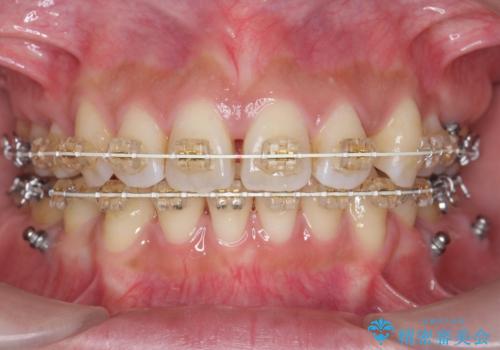

ガタつきと口元の改善 抜歯を伴うワイヤー矯正

- 唇の閉じづらさと、前歯のがたつきの改善を希望され来院されました。

抜歯を行わなくてもなんとか並べられる歯並びですが、唇の閉じづらさをしっかりと改善するため抜歯を伴うマルチブラケット矯正を行うこととしました。

前歯をしっかりと後方に引いたことで、唇は閉じやすくなり、仕上がりに満足いただくことができました。